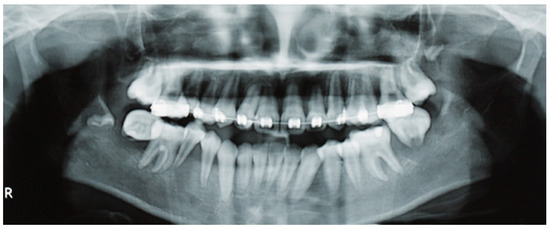

| 44 | Papadopoulou et al., 2024 (present case) | 11 | F | Painful swellings of the gingiva of the lower molars, tooth hypermobility, and facial asymmetry | Bilateral gingival swellings (erythematous and focally ulcerated) adjacent to mandibular premolars and molars that were hypermobile, displaced, and partially extruded Facial swelling along the right posterior mandible | Panoramic radiograph: ill-defined radiolucencies in the posterior mandible bilaterally, ‘floating-in-air’ teeth appearance CT: hypodense masses along and distal to the mandibular ramus extending upwards into the maxillary sinuses bilaterally, and the posterior wall of the right orbit; perforation of the right mandibular cortex | 11 years, no recurrence |